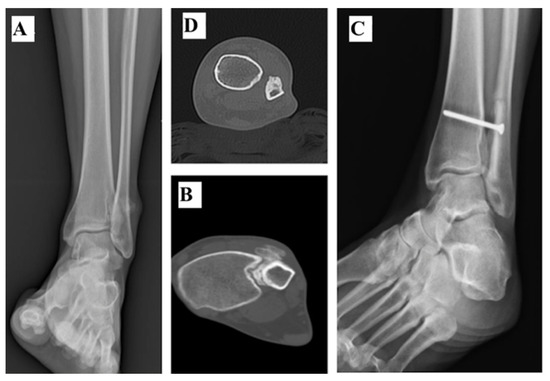

2.1. Tibiotalar Arthrodesis

| 1 | 133 | 7.5 | No | Yes | Yes | No | 0 | TTA | 3 | - | No | 27 |